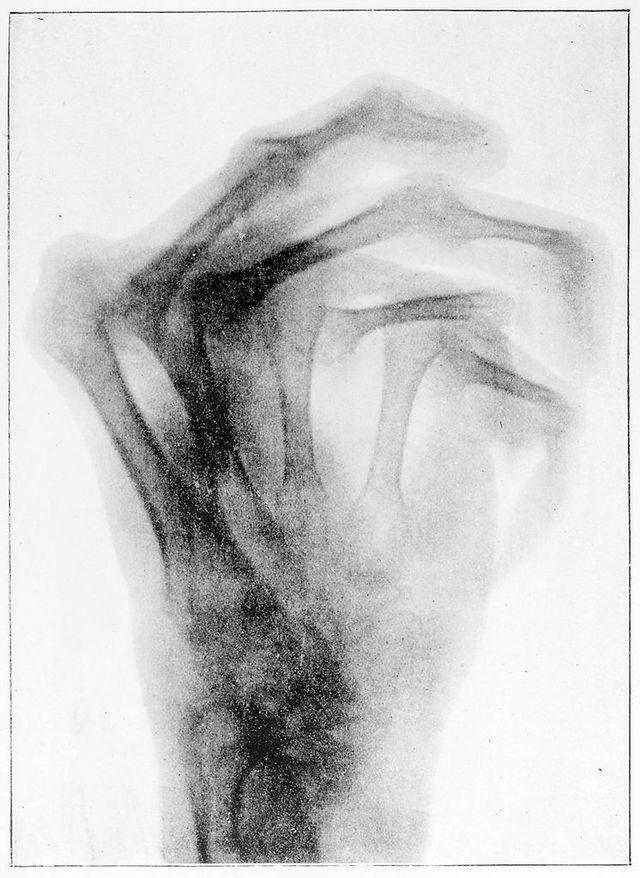

M0019124: X-ray of a hand deformed by osteo-arthritis, c.1897

Credit: M0019124: X-ray of a hand deformed by osteo-arthritis, c.1897. Source: Wellcome Collection.